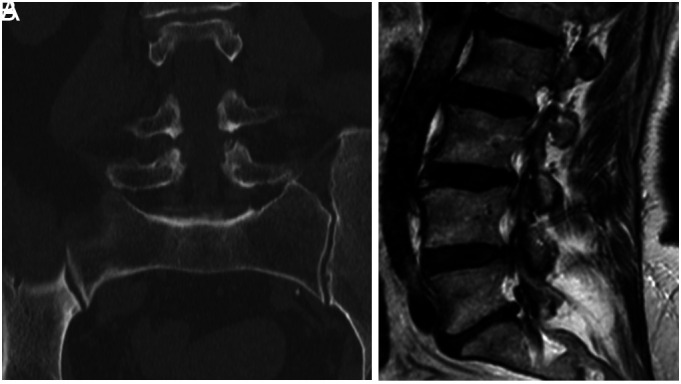

目的:本研究旨在探讨腰骶过渡椎体(LSTV)与腰椎间盘退变(Pfirrmann分级)之间的关系,腰骶过渡椎体(Castellvi's分级)与腰椎间盘退变(Pfirrmann分级)基于放射学评估。方法:本回顾性研究分析了2516例慢性腰痛患者(女性1548例,男性968例),平均年龄51.83±15.6岁,于2018年1月至2021年1月在单一中心接受腰骶部磁共振成像和计算机断层扫描。采用Pfirrmann分级评估L4-L5椎间盘退变,Castellvi分级确定LSTV的解剖类型。通过相关分析评估LSTV的存在与椎间盘退变之间的关系。此外,采用比例-几率有序逻辑回归模型来检验Pfirrmann分级与患者特异性因素(年龄、性别和LSTV存在)之间的关系。结果:按照Pfirrmann分级,ⅰ级113例,ⅱ级402例,ⅲ级877例,ⅳ级861例,ⅴ级263例。无LSTV 771例(30.6%),有LSTV 1745例(69.4%)。LSTV的存在与Pfirrmann分级之间有统计学意义的相关性(P < 0.001, r= 0.200)。与没有LSTV的患者相比,LSTV患者出现更高Pfirrmann分级的概率为0.75倍(95% CI: 0.58-0.90, P < .001)。然而,以Castellvi分类的LSTV亚型与Pfirrmann分级之间无显著相关性(P=.379)。此外,年龄与Pfirrmann分型、LSTV存在、Castellvi分型显著相关(P < 0.001)。女性患者出现Pfirrmann分级的可能性是男性患者的1.34倍(95% CI: 1.19-1.49, P < 0.001)。结论:本研究强调了LSTV与晚期椎间盘退变之间的显著关联,确立了LSTV是进行性脊柱改变的潜在危险因素。它强调了早期发现和有针对性的管理的重要性,特别是对于更容易发生严重退行性变化的老年人和女性。证据等级:III级,预后研究。

Objective: This study aimed to examine the relationship between lumbosacral transitional vertebra (LSTV), classified by Castellvi's system, and lumbar disc degeneration, graded using Pfirrmann's classification, based on radiological assessment. Methods: This retrospective study analyzed 2516 patients (1548 females and 968 males) with a mean age of 51.83 ± 15.6 years with chronic low back pain who underwent lumbosacral magnetic resonance imaging and computed tomography scans at a single center between January 2018 and January 2021. Pfirrmann grading was used to assess L4-L5 intervertebral disc degeneration, and Castellvi classification determined the anatomical type of LSTV. Correlation analysis was performed to evaluate the association between LSTV presence and disc degeneration. Additionally, a proportional-odds ordinal logistic regression model was used to examine the relationship between Pfirrmann grade and patient-specific factors (age, gender, and LSTV presence). Results: According to Pfirrmann classification, 113 patients were grade I, 402 were grade II, 877 were grade III, 861 were grade IV, and 263 were grade V. A total of 771 patients (30.6%) did not have LSTV, while the remaining 1745 patients (69.4%) had LSTV. A statistically significant association was found between LSTV presence and Pfirrmann grade (P < .001, r=.200). Patients with LSTV had 0.75 times higher probability (95% CI: 0.58-0.90, P < .001) of exhibiting a higher Pfirrmann grade compared to those without LSTV. However, no significant correlation was observed between LSTV subtypes classified by Castellvi and Pfirrmann grade (P=.379). Additionally, age was significantly correlated with Pfirrmann classification, LSTV presence, and Castellvi classification (P < .001). Female patients had 1.34 times higher likelihood (95% CI: 1.19-1.49, P < .001) of exhibiting a higher Pfirrmann grade compared to male patients. Conclusions: This study highlights the significant association between LSTV and advanced disc degeneration, establishing LSTV as a potential risk factor for progressive spinal changes. It emphasizes the importance of early detection and targeted management, particularly for older adults and females who are more susceptible to severe degenerative changes. Level of Evidence: Level III, Prognostic Study.